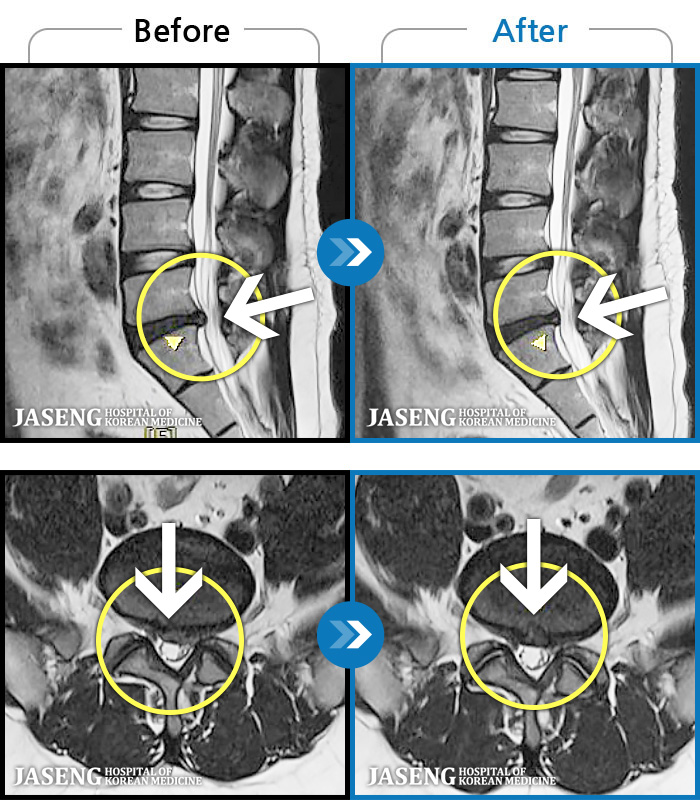

MRI ġ

1,245 MRI ũ ʸ Ȯϼ.